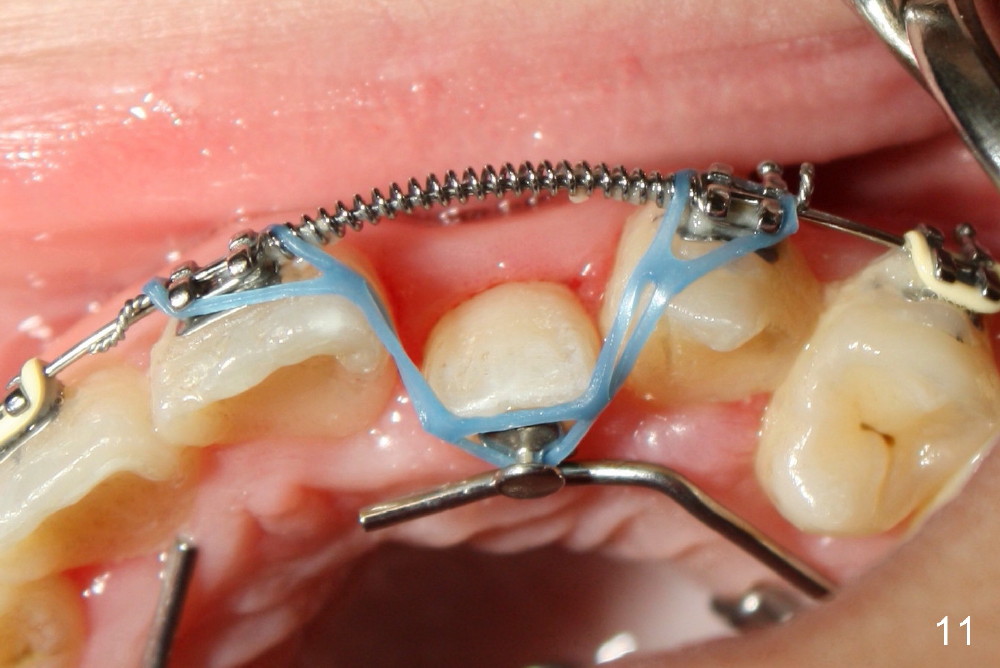

Two months installing open coil between UL 1 and 3, the space for UL2 is not increased enough. In addition, posterior cross bite is not corrected by arch expansion. Nitanium palatal expander is placed. One month later, the posterior cross bite appears to have been improved. The space for UL2 increases significantly (Fig.10); a sling shot is installed (Fig.11).